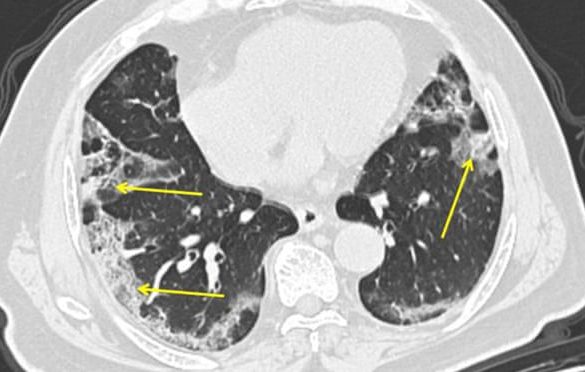

Pulmolozi objašnjavaju kako korona ubija kad stigne u pluća

Životi, koje je od decembra 2019. do danas odnio koronavirus, podlegli su bolesti onog…